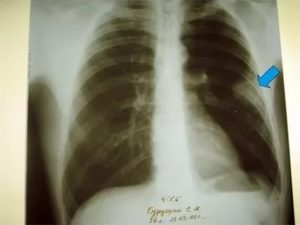

- Рентген. Проводится рентгенография в нескольких проекциях. Метод позволяет определить область поражения и характер процесса. На снимках патология проявляется затемнениями с размытыми контурами (на фото).

Плеврит легких на рентгенограмме

При необходимости дополнительно назначается рентген. Как правило, спайки располагаются в нижней части легкого. При этом будет более темная картинка, а также может быть частичная деформация грудной клетки и диафрагмы.